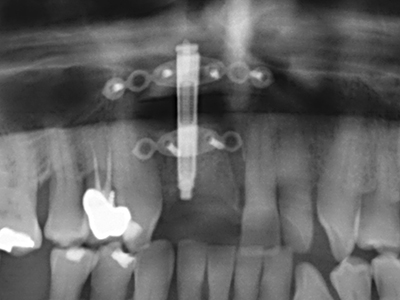

Fig. 11: El ortopantomograma posoperatorio presenta el aumento vertical y la elevación del suelo del seno.

Fig. 12: Después de seis meses de cicatrización se muestra una cresta maxilar vital con unas dimensiones suficientes en todas las direcciones.

Otras indicaciones

Fig. 25: Ortopantomograma después de alcanzar la altura de distracción final, antes del período de consolidación.